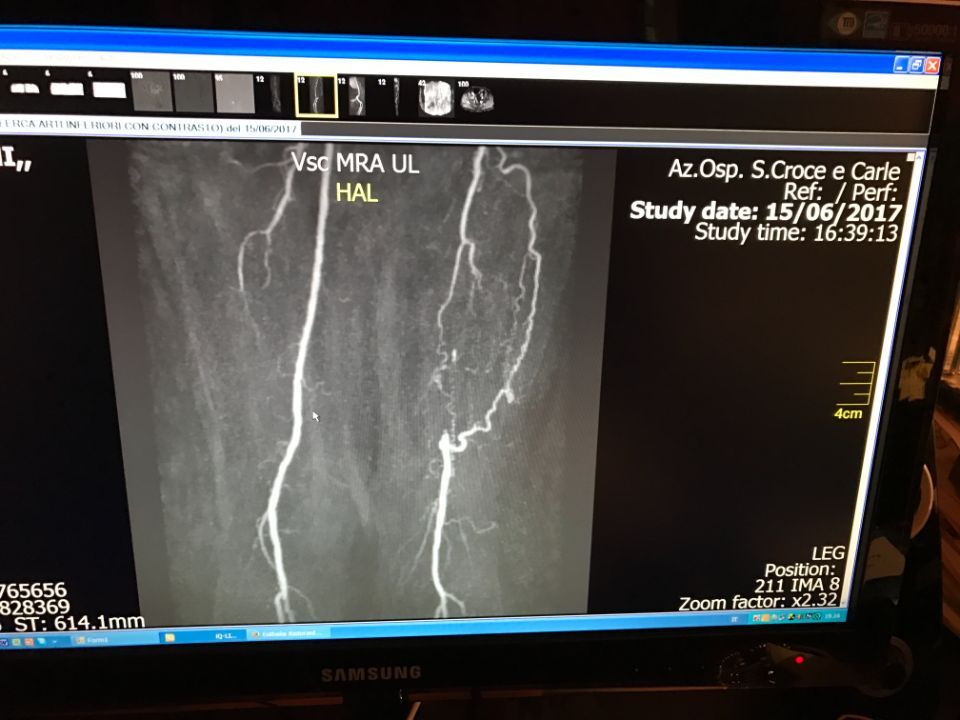

Ecco alcune immagini degli interventi eseguiti dal Dottor Viglione presso il suo studio a Cuneo.